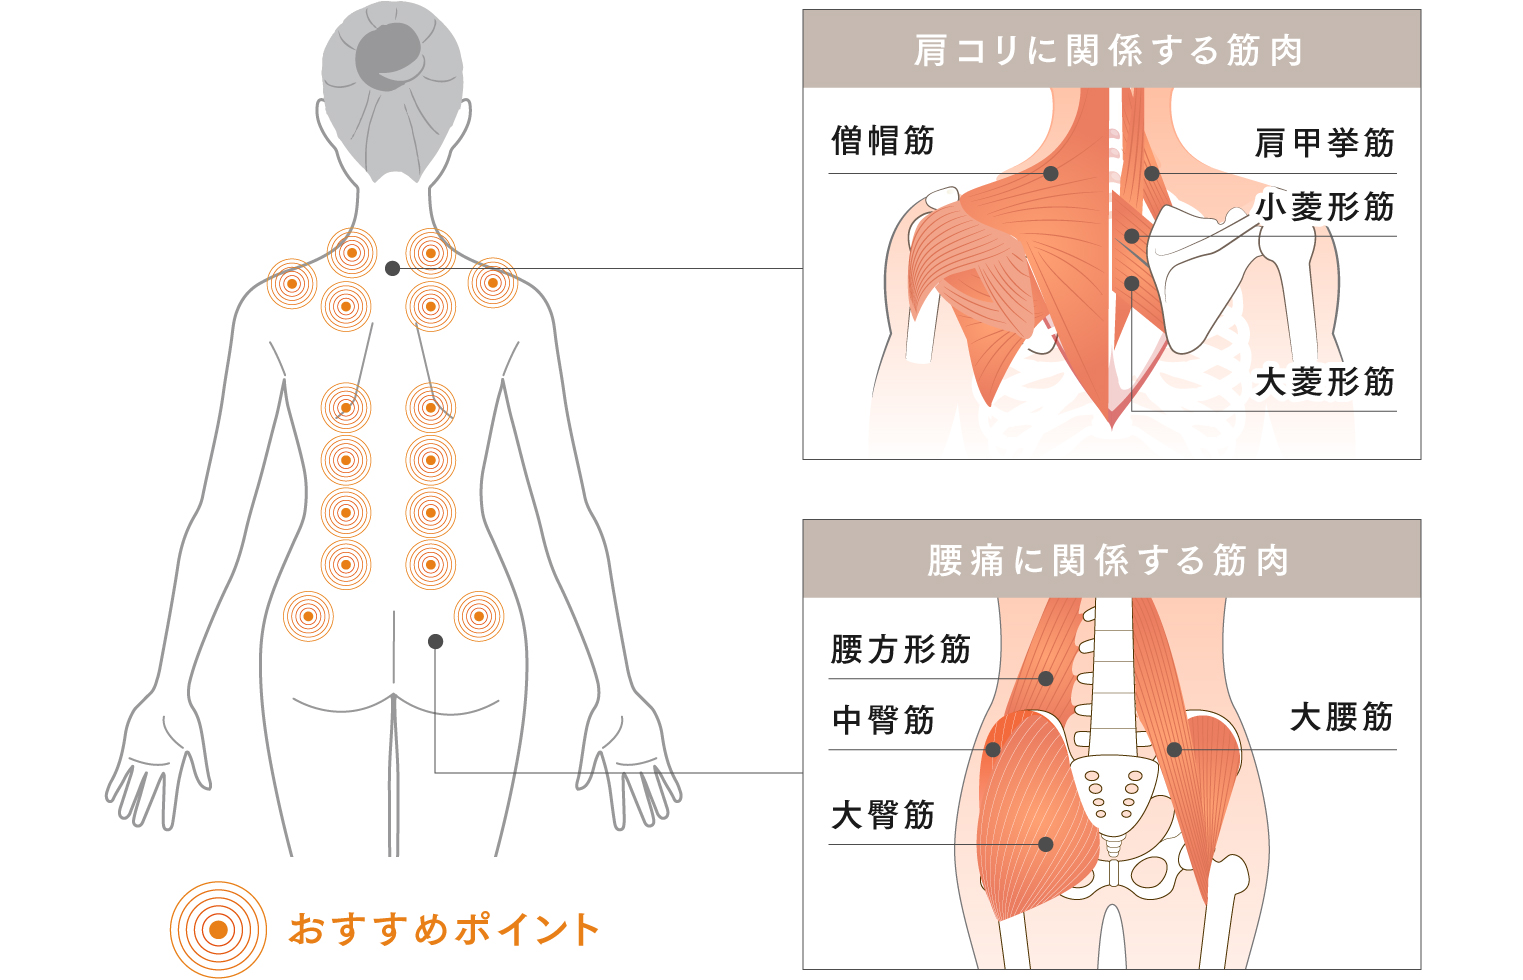

腰痛・肩コリは

最も身近な現代病

最も身近な現代病

腰痛や肩コリは現代病とも呼ばれ、国民生活基礎調査の「体の不調ランキング」で男女ともに1,2位にあがっています。「ONCURE」は血行不良からくるコリや筋肉の痛みをピンポイントに狙って血行を促進し、コリや痛みを治療します。

深くまで届く温熱効果で

気になる肩コリ・腰痛の

根本原因をピンポイントに治療

気になる肩コリ・腰痛の

根本原因をピンポイントに治療

コリ・痛みの

発生原因

発生原因

健康な筋肉

筋肉が柔らかく、血管が広がっていて血行も良好な状態。

コリの発生した筋肉

筋肉が硬くなり、血管を圧迫。血行不良にになると、脳がコリを認識。